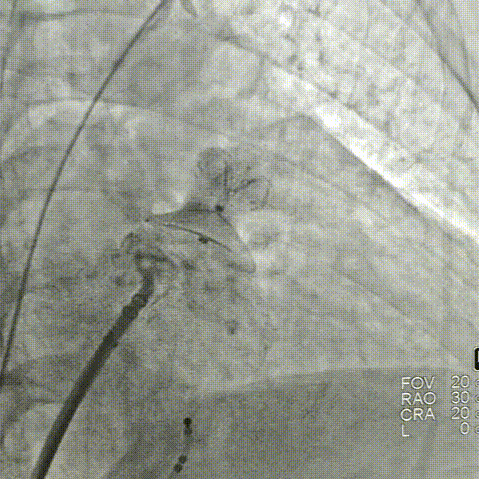

符合COVER原则,将LAMax LAAC®2436 Plus封堵器释放,再次DSA造影检查,封堵器形态无变化,封堵效果好。

释放后封堵效果满意